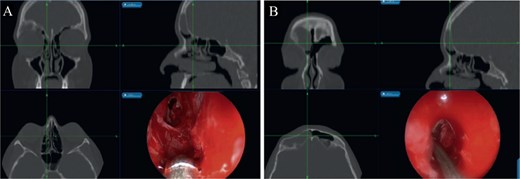

Bilateral extensive nasal polyposis was removed, and pus was drained from the ethmoid sinus cavities using a microdebrider (Fig. 2). Draf type IIb procedure was performed bilaterally to facilitate frontal sinus drainage and ventilation. The procedure was followed by antibiotic-soaked irrigation and evacuation of both mucopyocele cavities. After 6 months, the patient came to the clinic for follow-up, and his repeated CT scans showed normal sinus aeration and complete resolution.

Bilateral frontal sinus showing infected nasal polyps, identified intraoperatively, and drained by image-guided endoscopic sinus surgery.